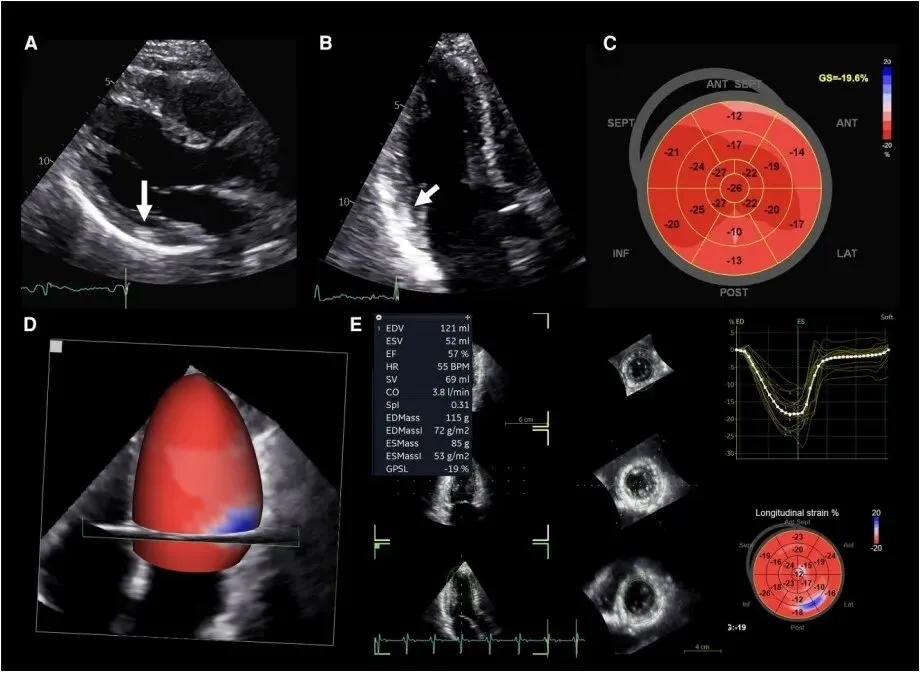

图4 法布雷病多模态成像分析的代表性病例

标准和斑点追踪超声心动图以及心脏磁共振成像结果;PL:后外侧;LGE:晚期钆增强。

图5 57岁有FC家族史患者的二维和三维超声心动图早期心脏受累表现

ANT:前壁;SEP:室间隔;INF:下壁;LAT:侧壁;POST:后壁;GS:应变。